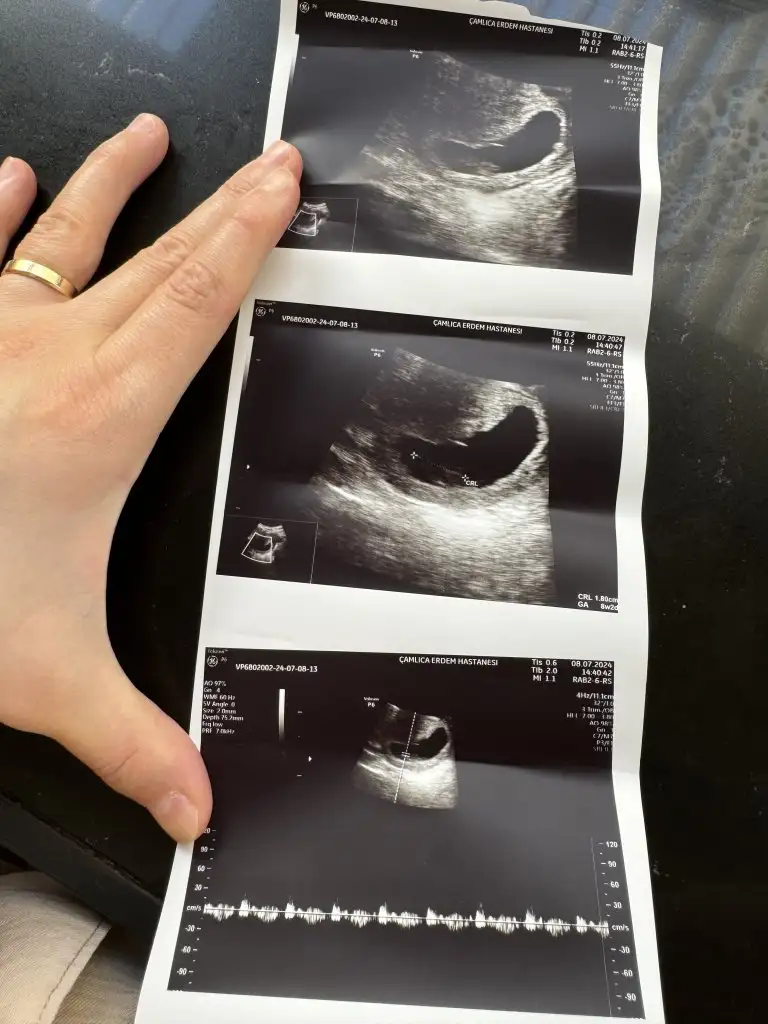

Evet kuzum ultrasyonda 8 haftalık suan 9 olmuştur , ınan hamılelıgım oğlumda gecırdıgım gibi deıl , oğlumda sureklı ekşi yerdim kısır şalgam turşu ağırlıklı tüketirdim ve sadece mide bulantım olurdu , ama bu hamılelıkte sureklı uyku bas donmesi sivilcelenme tatlı türü yeme isteği ekşi aramıyorum da , 2 sayfaya ınstgramda ultrasyon attım %70 %80 erkek dedi yanılma durumları da varmış , sadece merak sağlıklı olsun ama , artık pes ettim çevrem sureklı uyuduğum için kızın olacak diyor ama anlamadım gitti karışık yani😂

• image.webp

image.webp

28,9 KB · Görüntüleme: 108